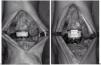

Figura 5. Prótesis total implantada. (A) flexión dorsal. (B) flexión plantar. Obsérvese el deslizamiento de la pieza intermedia.